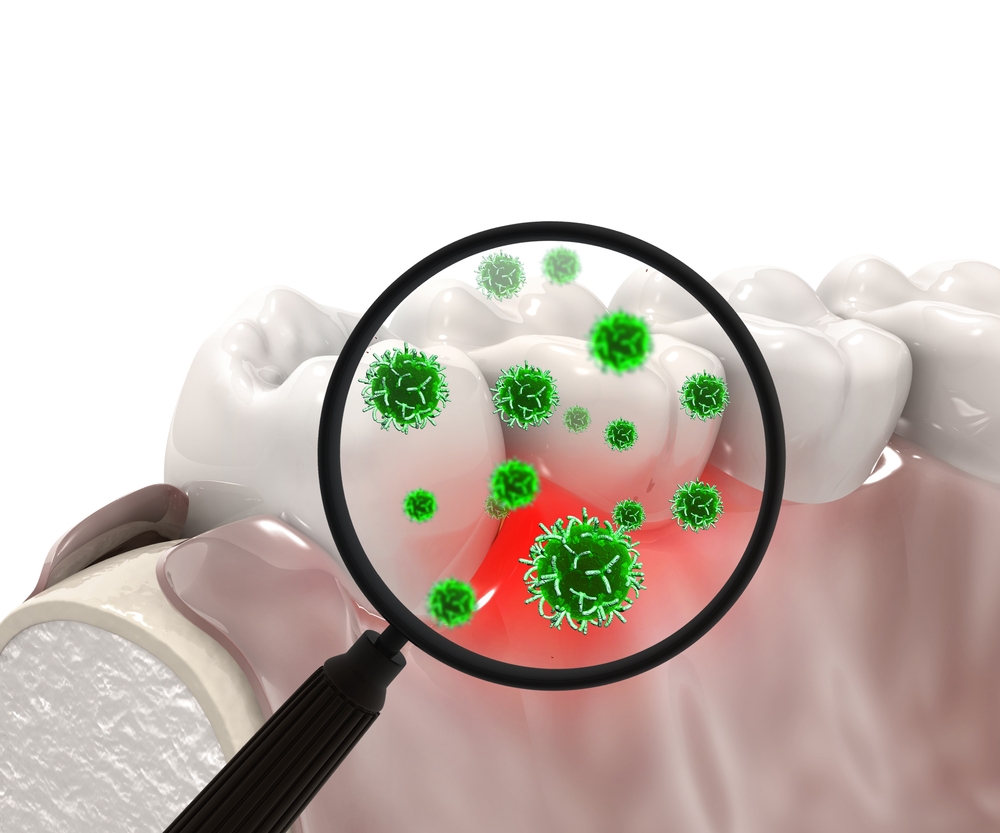

Placa bacteriană este o peliculă subțire care se formează continuu la baza dinților și este formată în principal din particule alimentare, salivă și bacterii, având o textură moale și o culoarea albicioasă, uneori chiar gălbuie. Aceasta încorporează constant materiile anorganice din salivă , în principal sărurile de calciu. Astfel, placa bacteriană se transformă, în timp, dintr-un depozit moale, într-un depozit dur numit tartru dentar.

Tartrul acționează ca un mic țep iritativ pentru gingii determinând sângerare gingivală, inflamație și retractie gingivală. Fiind un depozit ce stă pe suprafața dentară poate masca cariile deja existente, oferindu-le un mediu propice pentru dezvoltare. Din păcate, tartrul nu poate fi îndepărtat prin regimul obișnuit de igienă orală la domiciliu, ci se tratează doar prin profilaxie profesională, realizată în cabinetul stomatologic.